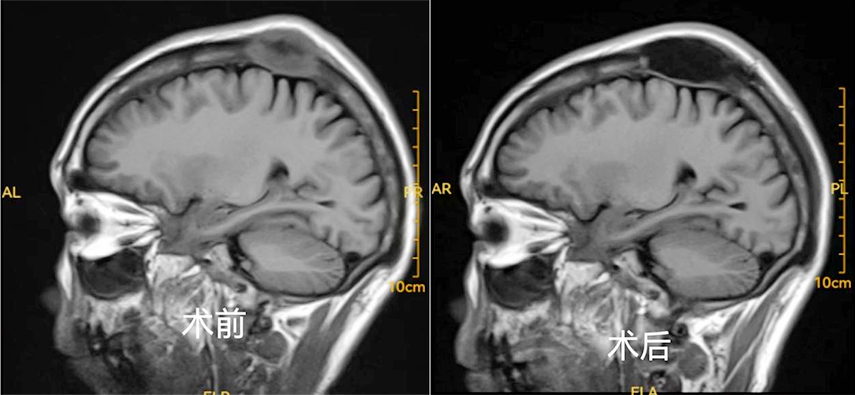

近日,兰大二院帮扶岷县人民医院医疗队完成该院首例颅骨肿瘤切除术,填补了岷县人民医院该项技术的空白。

患者男性,50岁,一年前诊断为肺部恶性肿瘤,因头顶部肿物进行性增大并伴头痛13天余再次入院检查。经相关化验并结合CT检查,考虑诊断为肺部恶性肿瘤颅骨转移,手术治疗指征明确,无手术禁忌症。兰大二院帮扶队员梁文涛及岷县人民医院神经外科主任马旭春团队综合评估后决定实施颅骨肿瘤切除术,术后患者生命体征平稳,恢复良好。